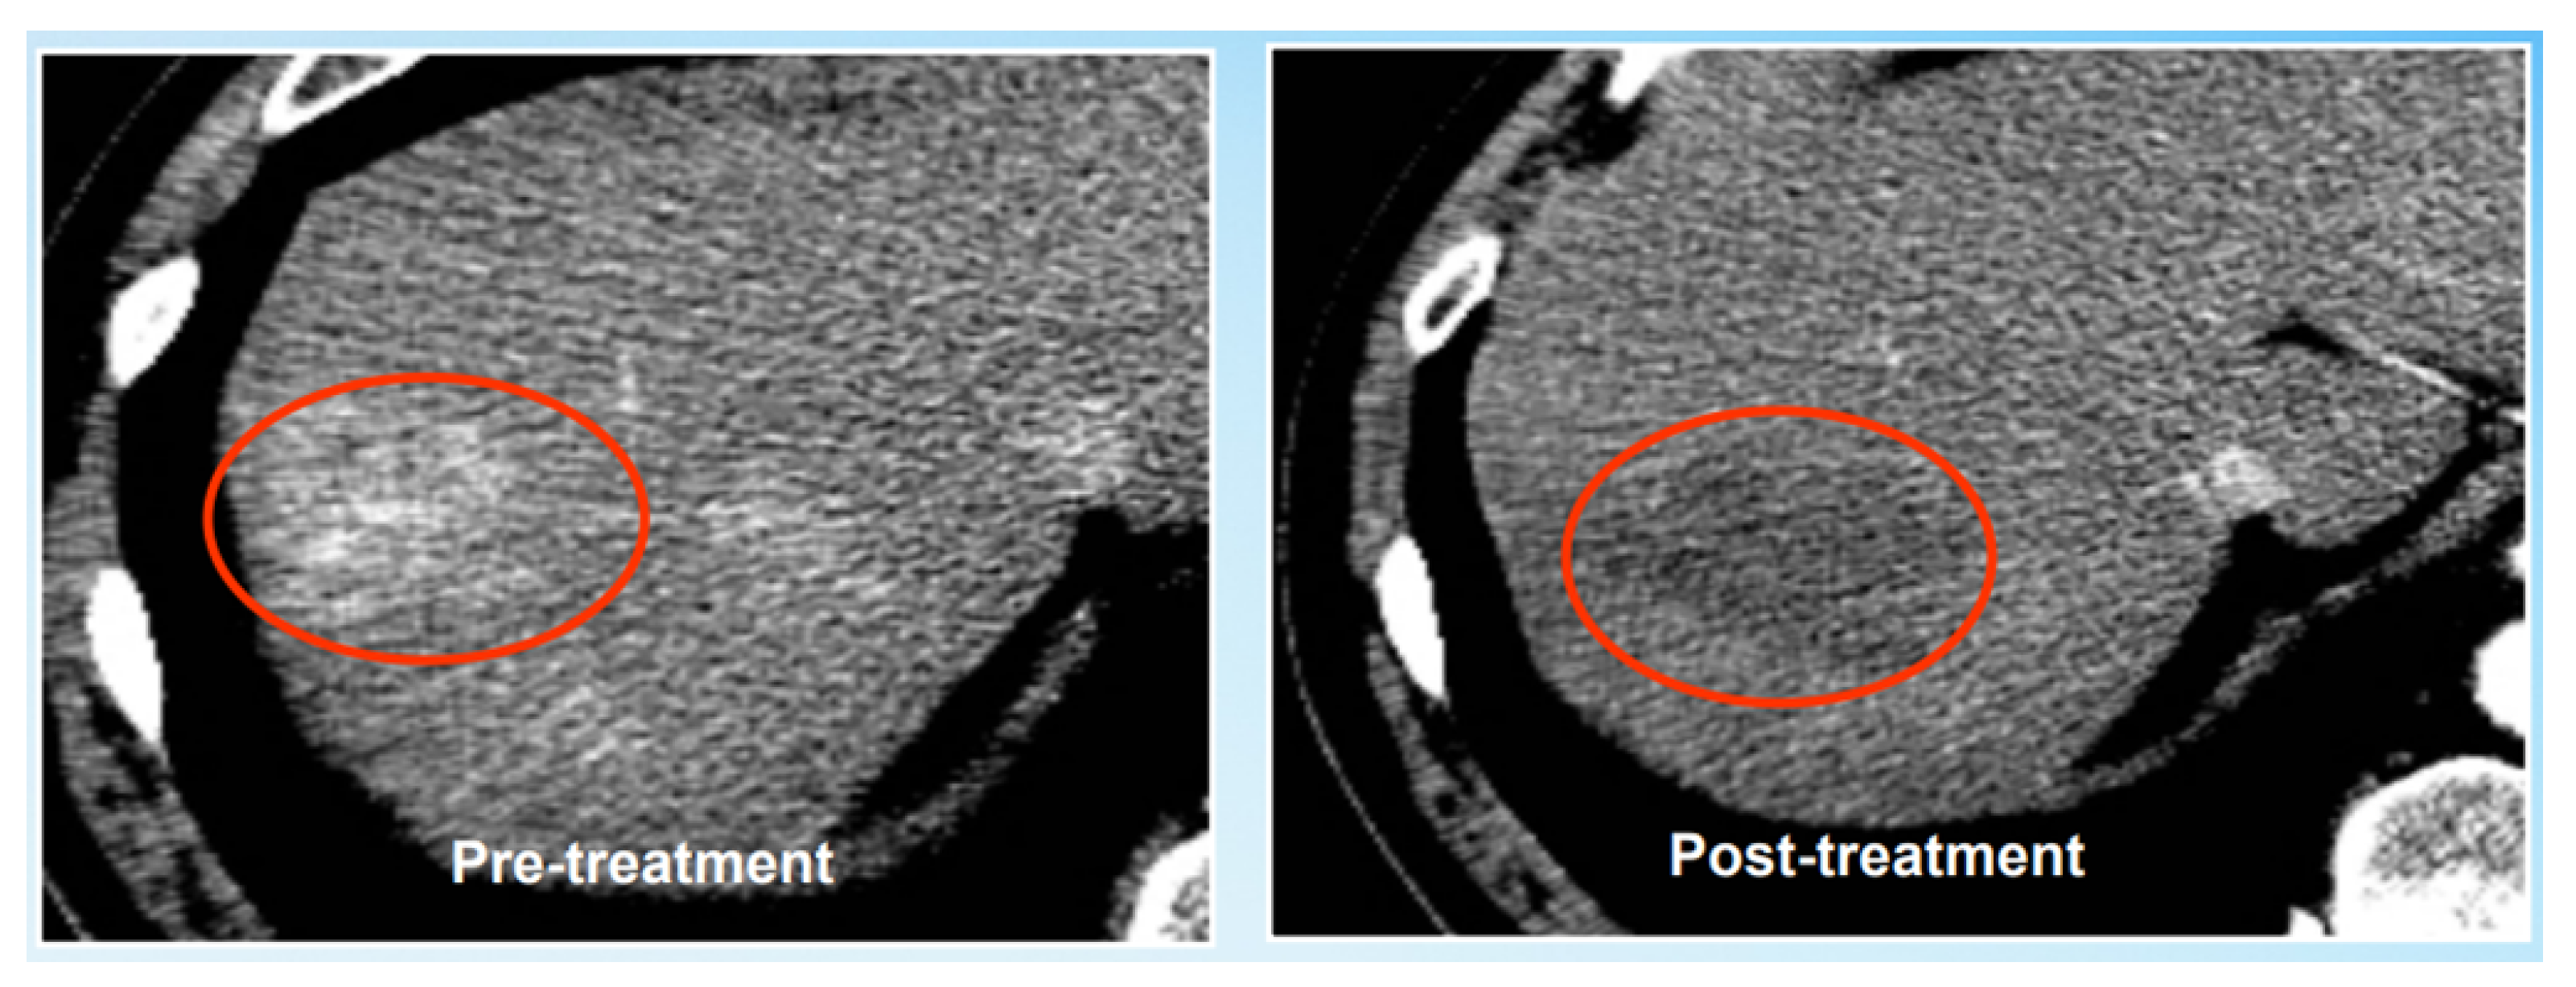

- Gonzalez-Guindalini, F.D.; Botelho, M.P.; Harmath, C.B.; Sandrasegaran, K.; Miller, F.H.; Salem, R.; Yaghmai, V. Assessment of liver tumor response to therapy: Role of quantitative imaging. Radiographics 2013, 33, 1781–1800. [Google Scholar] [CrossRef]